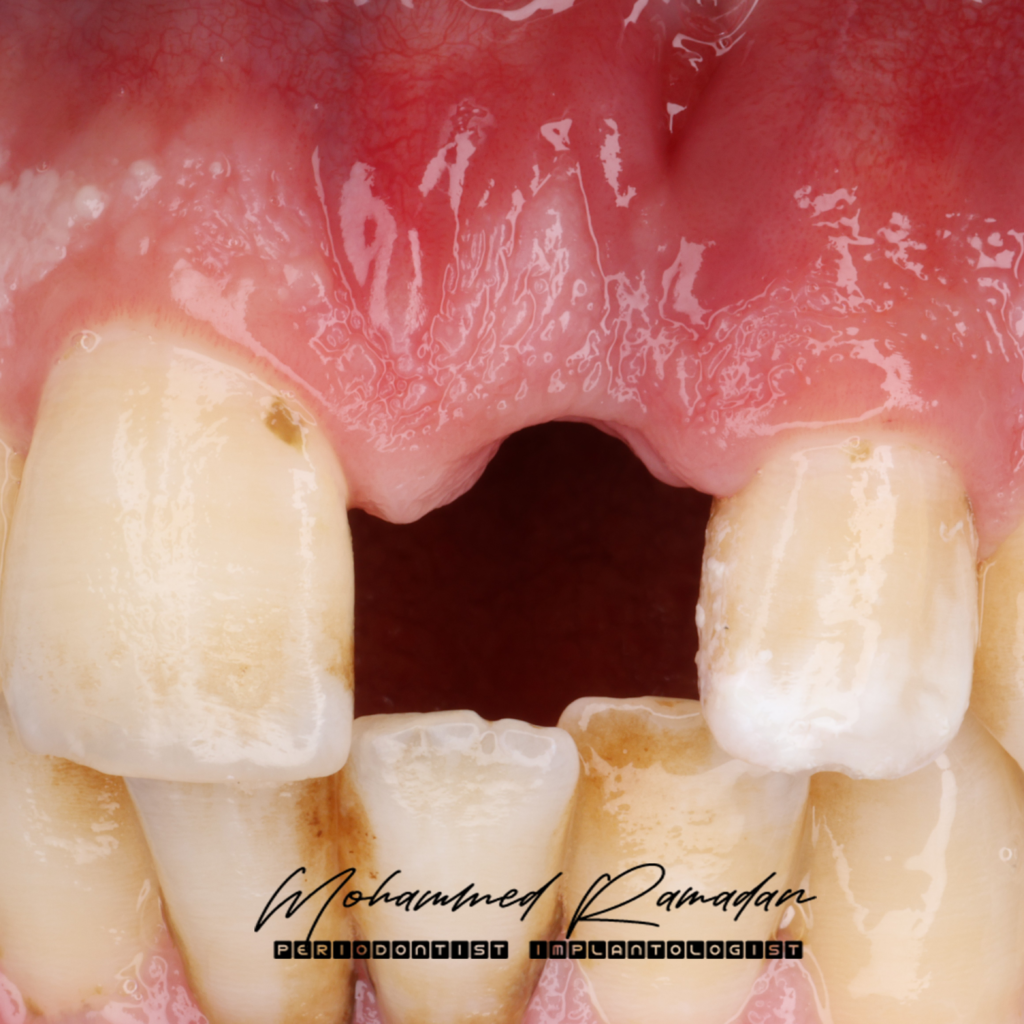

Clinical Examination

- Findings: Absence of the maxillary left central incisor

- Chief Complaint: Esthetic concern due to missing anterior tooth